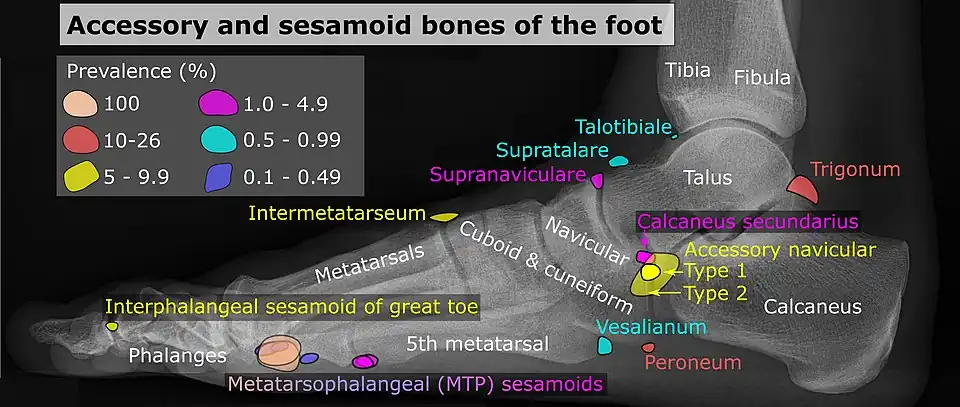

Foot

| Bone | Prevalence[17] |

|---|---|

| Sesamoid bones | |

| Sesamoids at the metatarsophalangeal (MTP) joint of the great toe | Always present |

| Sesamoid of the second metatarsal | 0.4% |

| Sesamoid of the third metatarsal | 0.2% |

| Sesamoid of the fourth metatarsal | 0.1% |

| Sesamoids of the fifth metatarsal | 4.3% |

| Sesamoid of the interphalangeal (IP) joint of the great toe | 2–13% |

| Ossicles | |

| Os trigonum (not visible in this dorsoplantar projection) | 7–25% |

| Os peroneum | Up to 26% |

| Accessory navicular | 2–21% |

| Os intermetatarseum | 1–13% |

| Os supranaviculare, also called the talonavicular bone | 1.0–3.5% |

| Os calcaneus secundarium | 0.6–7% |

| Os supratalare | 0.2–2.4% |

| Os vesalianum | 0.1–1% |

| Os talotibiale | 0.5% |

Accessory navicular

An accessory navicular bone, also called os tibiale externum, occasionally develops in front of the ankle towards the inside of the foot. This bone may be present in approximately 2–21% of the general population and is usually asymptomatic.[18][19][20] When it is symptomatic, surgery may be necessary.

The Geist classification divides the accessory navicular bones into three types.[20]

- Type 1: An os tibiale externum is a 2–3 mm sesamoid bone in the distal posterior tibialis tendon. Usually asymptomatic.

- Type 2: Triangular or heart-shaped ossicle measuring up to 12 mm, which represents a secondary ossification center connected to the navicular tuberosity by a 1–2 mm layer of fibrocartilage or hyaline cartilage. Portions of the posterior tibialis tendon sometimes insert onto the accessory ossicle, which can cause dysfunction, and therefore, symptoms.

- Type 3: A cornuate navicular bone represents an enlarged navicular tuberosity, which may represent a fused Type 2 accessory bone. Occasionally symptomatic due to bunion formation.

Os trigonum

The os trigonum or accessory talus represents a failure of fusion of the lateral tubercle of the posterior process of the talus bone. Is estimated to be present in 7–25% of adults.[17] It can be mistaken for an avulsion fracture of lateral tubercle of talus (Shepherd fracture) or a fracture of the Stieda process. In most cases, Os Trigonum will go unnoticed, but with some ankle injuries it can get trapped between the heel and ankle bones which irritates the surrounding structures, leading to Os Trigonum Syndrome.[21]